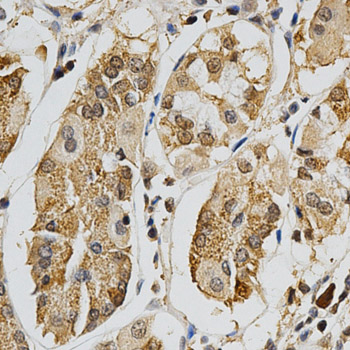

Immunohistochemistry of paraffin-embedded human stomach using MAPK10 antibody at dilution of 1:200 (x400 lens)